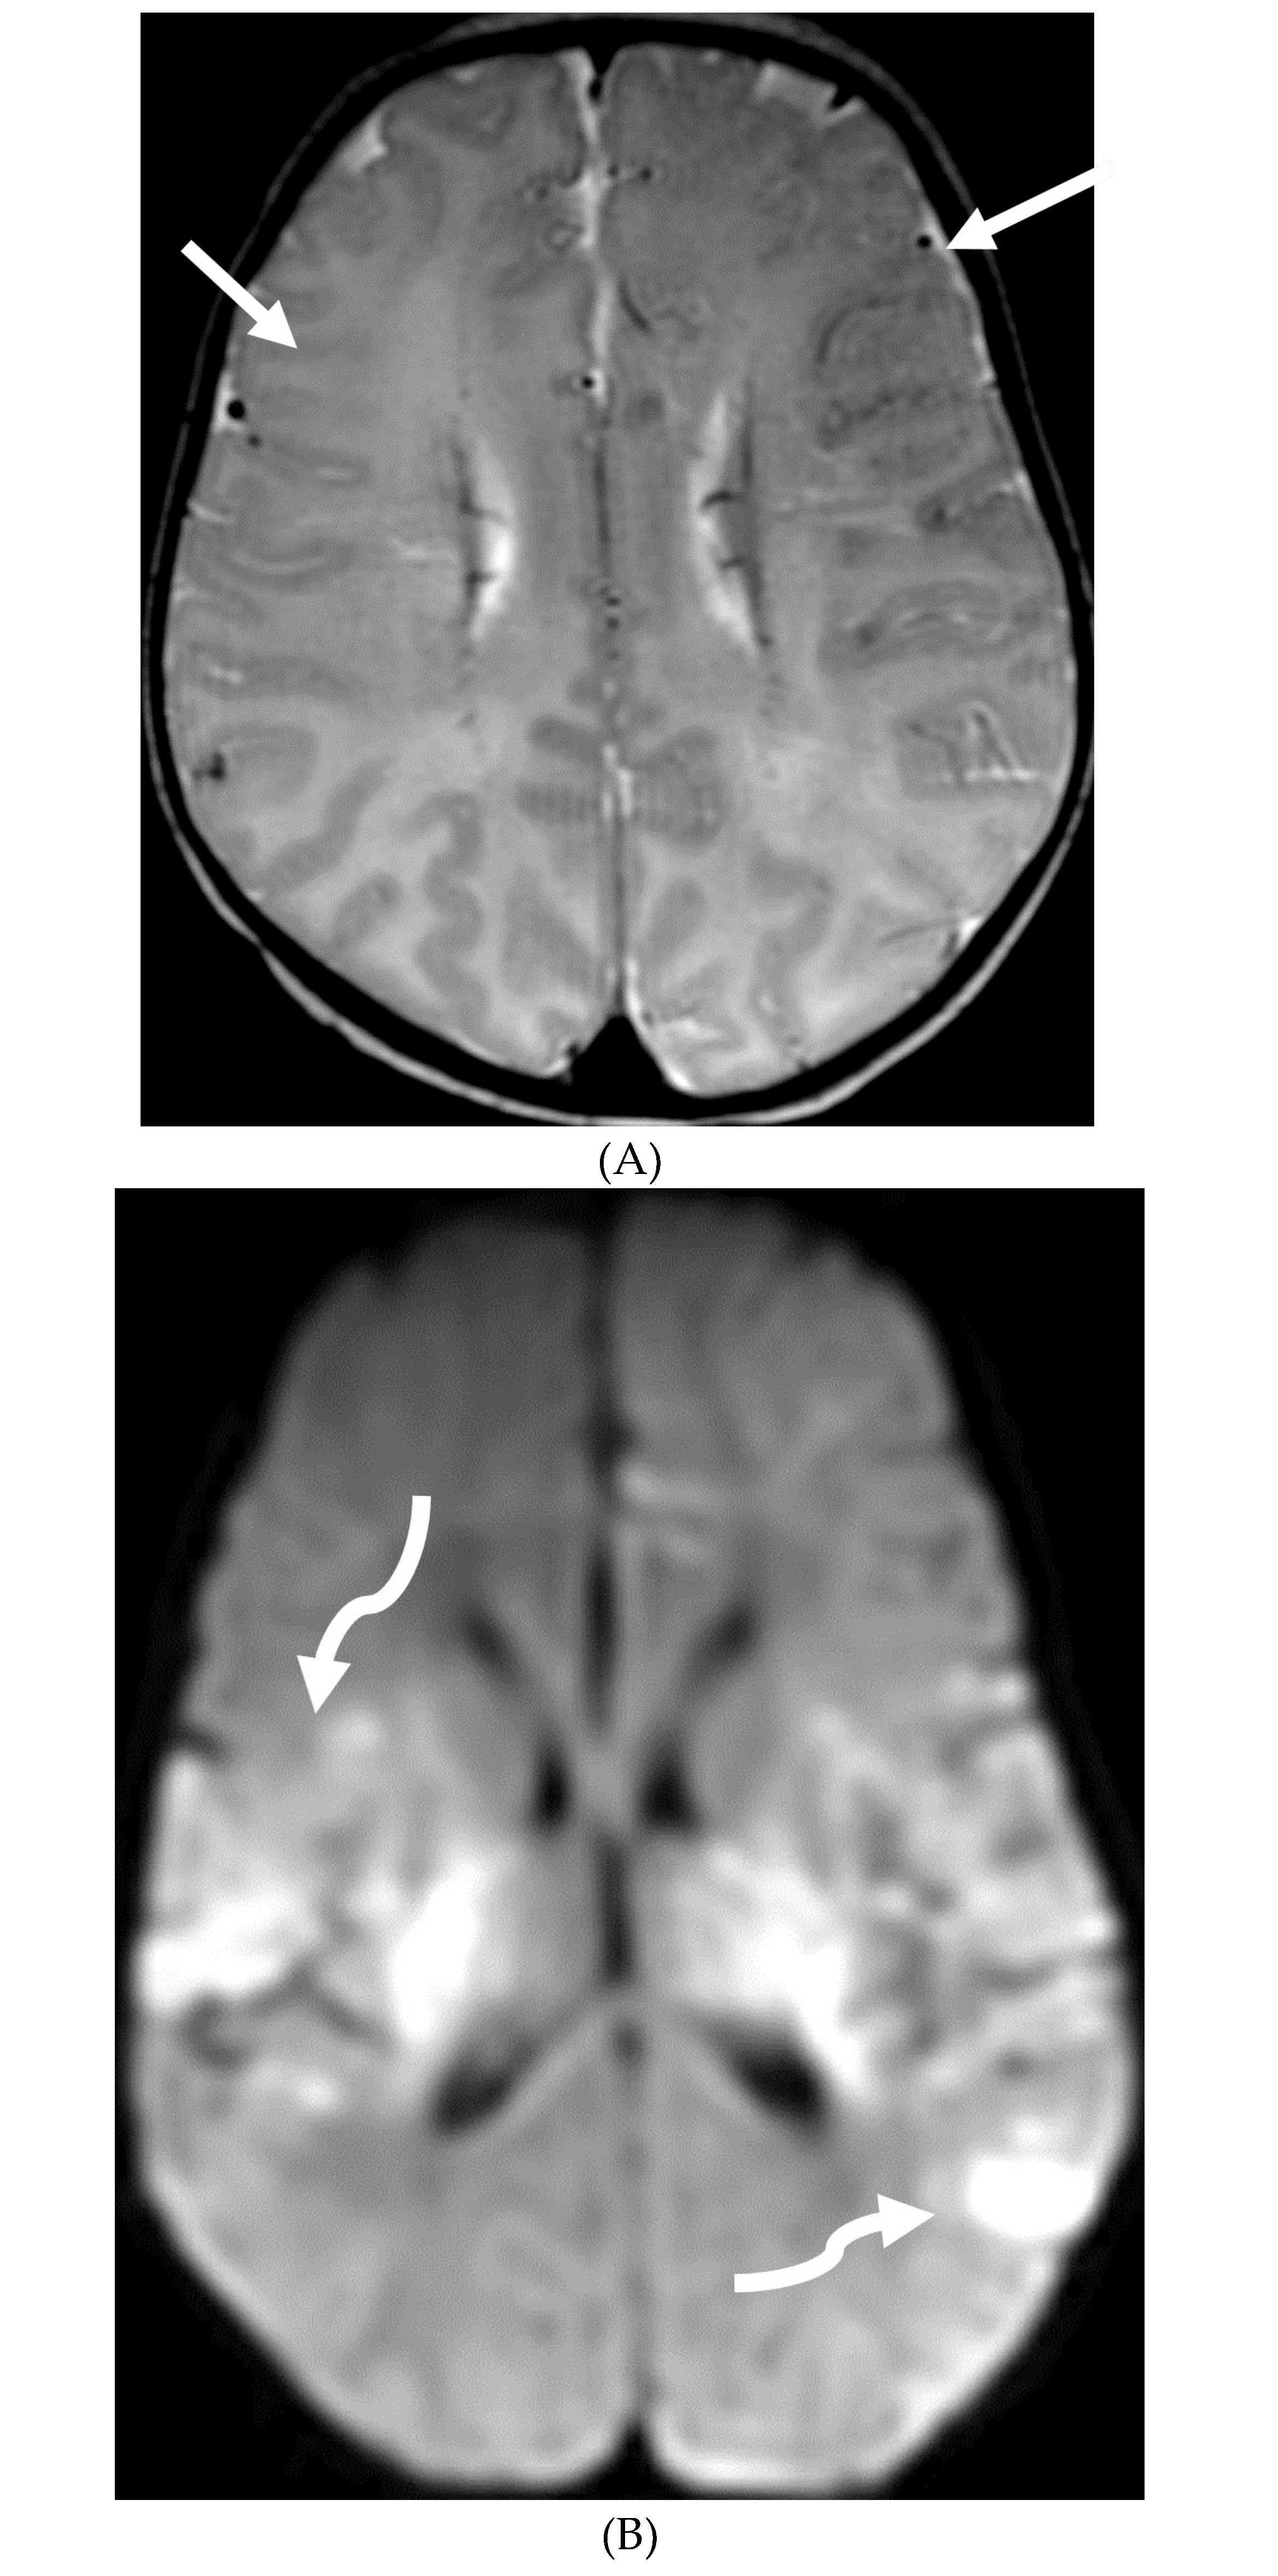

PIAL ANGIOMATOSIS